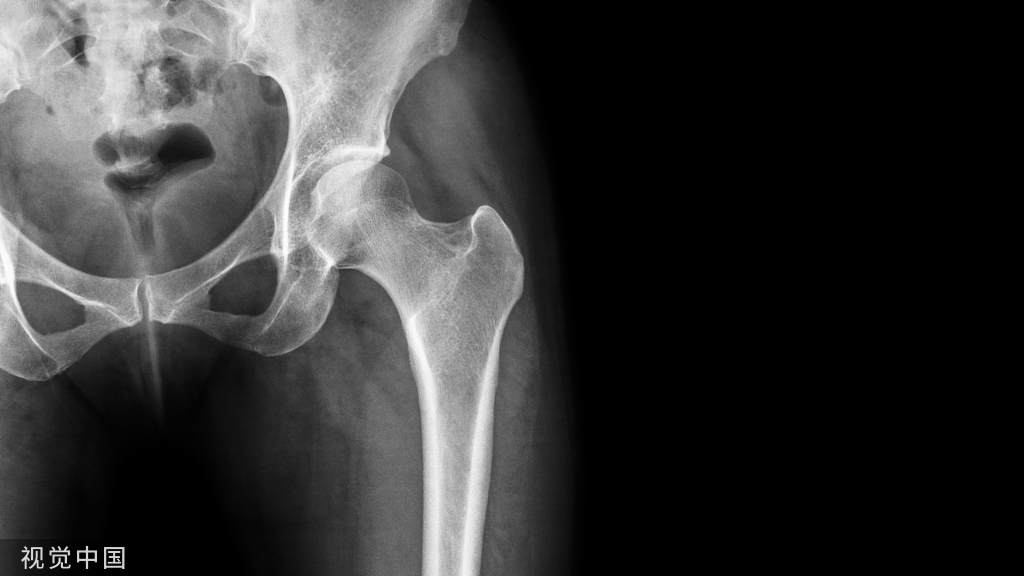

1、术前拍X片,了解尖周病变和牙根吸收情况。牙根吸收已达1/3以上者,难获良好的疗效。

2、预备根管时应测根管长度以防器械超出根尖孔,以免将感染物质推出根尖孔或损伤恒牙胚。

5、术后应拍X片观察根充情况,分类:

①适充填:恰填或距根<1mm;

②欠充填:糊剂未充满根管,距根尖孔>1mm;

③超充填:糊剂超出根尖孔。

3、X线显示病变消失或原有阴影缩小,超出糊剂已完全吸收,恒牙胚无异常发育。

2、X线显示:牙根病理性吸收或病变扩大等。